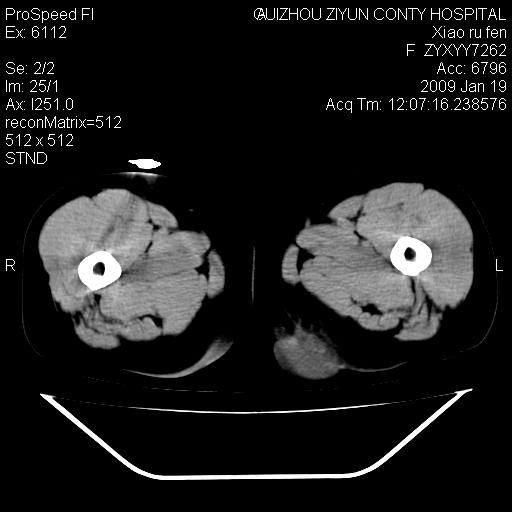

以下是引用随光逐影在2009-1-19 16:15:00的发言:[br]左侧臀部类似软组织密度肿块,性质待定(不排除肿瘤可能);建议行进一步检查。

以下是引用zbp537在2009-1-19 14:25:00的发言:[br]考虑两个诊断:1、皮脂腺囊肿伴感染。2、脓肿。[br]诊断依据:[br]1、肿块为低密度,边界较清,和皮肤相连,周围结构清晰,未见受累及。[br]2、诊断脓肿是因为其内密度不均匀,当然要结合病史,因为脓肿临床上肯定表现为红肿热痛,也希望楼主把病史提供全面些,这些便于讨论。

以下是引用zbp537在2009-1-19 14:25:00的发言:[br]考虑两个诊断:1、皮脂腺囊肿。2、脓肿。[br]诊断依据:[br]1、肿块为低密度,边界较清,和皮肤相连,周围结构清晰,未见受累及。[br]2、诊断脓肿是因为其内密度不均匀,当然要结合病史,因为脓肿临床上肯定表现为红肿热痛,也希望楼主把病史提供全面些,这些便于讨论。